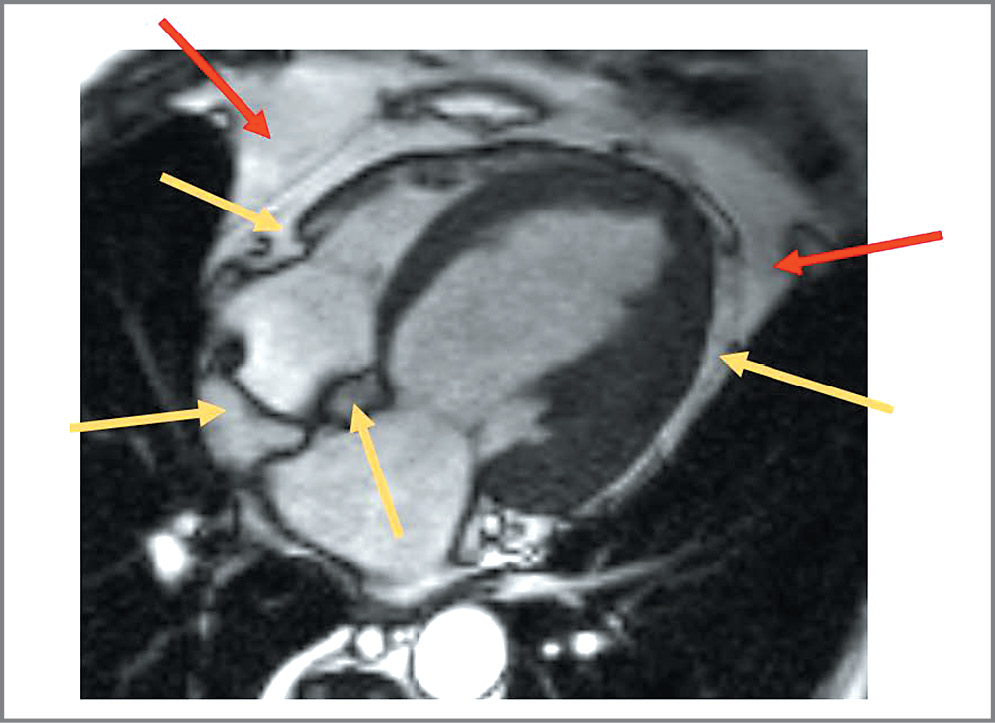

По данным лабораторных исследований обращает на себя внимание неадекватный контроль глюкозы: глюкоза крови 10,22 ммоль/л (при принятой в лаборатории норме 5,80 ммоль/л). Показатели липидного профиля на терапии аторвастатином 20 мг: общий холестерин – 4,5 ммоль/л, триглицериды – 3,48 ммоль/л, холестерин липопротеинов низкой плотности – 1,91 ммоль/л, холестерин липопротеинов высокой плотности – 1,01 ммоль/л. Уровень содержания трансаминаз в крови в пределах нормы, аспартатаминотрансфераза – 17,0 Ед/л; аланинаминотрансфераза – 20,0 Ед/л (при норме, принятой в лаборатории, 29 Ед/л). Нормальные показатели в крови уровня гормонов щитовидной железы исключили гипотиреоз как причину увеличения массы тела. На электрокардиограмме зарегистрирован синусовый ритм с частотой сердечных сокращений – 70 уд/мин, полная БЛНПГ. Эхокардиографическое исследование проведено на ультразвуковой системе экспертного класса VividE 9 с использованием фазированного датчика М5Sc-D и матричного датчика 4V-D (трехмерный режим); выполнена тканевая допплерография сердца для комплексной оценки диастолической функции желудочков (включая показатели Е/А, Е/Е`, Eml, Ems, Et). Фракция выброса и объемы ЛЖ рассчитывали биплановым методом дисков (модифицированный метод Симпсона в В-режиме). Размеры и объемы полостей сердца индексировали на площадь поверхности тела и соотносили с нормативными значениями. По данным ЭхоКГ, на фоне полной БЛНПГ определялось расширение ЛП и ЛЖ: ПЗР ЛП – 4,6 см (норма 2,7–3,8 см), апикально 5,4×4,7 см (норма 5,3×4,0 см); объем ЛП – 80 мл (норма до 52 мл); индекс объема ЛП 37,6 мл/м2 (норма до 34 мл/м2); конечно-диастолический размер ЛЖ в базальных отделах – 6,3 см (норма 3,8–5,2 см), в средних отделах – 7,9 см; конечно-систолический размер ЛЖ – 6,7 см (норма 2,2–3,5 см). Правое предсердие визуально не расширено, правый желудочек не расширен: ПЗР 2,7 см (норма до 2,9 см). Сократительная функция миокарда ЛЖ снижена: фракция выброса – 35%. Стенки ЛЖ умеренно утолщены: толщина межжелудочковой перегородки – 1,1 см; толщина задней стенки ЛЖ – 1,1 см (норма 0,6–0,9 см). Масса миокарда ЛЖ увеличена – 477,7 г (норма до 162 г); индекс массы миокарда ЛЖ увеличен – 224,3 г/м2 (норма до 95 г/м2). Умеренное повышение систолического давления в легочной артерии до 35 мм рт. ст. (норма до 30 мм рт. ст.). Скорость и время трансмитрального потока свидетельствуют о замедленной релаксации. Асинхронно движется переднеперегородочная область, очевидно, из-за наличия БЛНПГ. На фоне БЛНПГ не удается выявить четкую зону нарушения сократимости миокарда ЛЖ. Общая сократимость миокарда ЛЖ снижена. Нарушена диастолическая функция миокарда ЛЖ. По данным магнитно-резонансной томографии (МРТ) с контрастным усилением, на фоне внутривенного введения гадолиния выявлено расширение камер ЛЖ (конечно-диастолический размер ЛЖ составил 6,1–6,3 см), асинхронное сокращение миокарда межжелудочковой перегородки, по-видимому, за счет БЛНПГ. Нарушений сегментарной сократимости миокарда ЛЖ не выявлено. Очагового поражения миокарда желудочков ишемического или воспалительного генеза не выявлено. ПЗР ЛП составил – 4,1 см, толщина межжелудочковой перегородки – 1,1 см, толщина задней стенки ЛЖ – 0,9 см. Также выявлены липоматоз межпредсердной перегородки (МПП), скопление избыточного количества жировой ткани в полости перикарда вдоль свободной стенки правого желудочка, верхушки сердца и правой атриовентрикулярной борозды толщиной до 12 мм. Объем перикардиального жира составил 187 см3, в том числе в области МПП – 30,1 см3 (рис. 1, 2).

Рис. 1. МРТ сердца: Т1-взвешенные изображения, поперечная плоскость на уровне желудочков сердца. Красная стрелка указывает на паракардиальный жир (внутригрудной), желтая – эпикардиальный жир.

Fig. 1. Cardiac magnetic resonance imaging (MRI): T1-weighted images, transverse plane at the level of heart ventricles. The red arrow indicates paracardial fat (intrathoracic), the yellow arrow indicates epicardial fat.